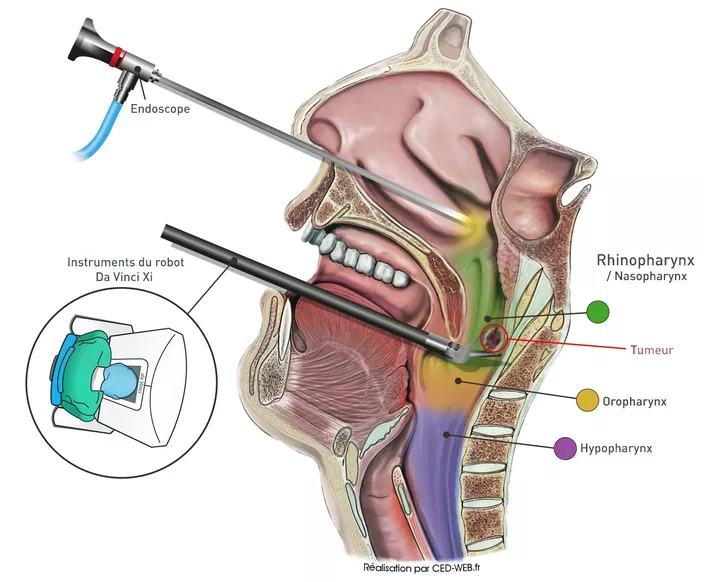

Découvrez notre collection unique d’illustrations conçues pour le domaine médical et scientifique. Chaque création combine rigueur scientifique et créativité artistique, offrant des visuels clairs et pédagogiques pour simplifier des concepts complexes.

De l’anatomie humaine aux processus biologiques, nos illustrations sont idéales pour enrichir des supports de communication, des publications académiques, des présentations professionnelles ou encore des formations en ligne.

Chaque projet est réalisé avec soin, en collaboration étroite avec des experts, afin de garantir une précision scientifique et une esthétique soignée.

Ce portfolio reflète notre passion pour la vulgarisation scientifique et notre engagement à transformer des connaissances spécialisées en outils accessibles et impactants.